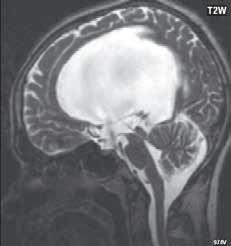

Obr. I.1.8a Dandy-Walkerova malformace, rozšířená IV komora (tvar klíčové dírky)

Obr. I.1.8b Dandy-Walkerova malformace, rozšířená IV komora široce komunikující s cisterna magna, hypotrofie mozečku (snímky zapůjčeny z archivu prim doc MUDr M Mechla, Ph D, MBA)

Obr. I.1.8c Dandy-Walkerova malformace, rozšířená IV komora široce komunikující s cisterna magna, hypotrofie mozečku (snímky zapůjčeny z archivu prim doc MUDr M Mechla, Ph D, MBA); stejný pacient jako na obr I 1 8b

Obr. I.1.8d Dandy-Walkerova malformace, rozšířená IV komora široce komunikující s cisterna magna, hypotrofie mozečku, vysoký úpon tentoria (šipka) (snímky zapůjčeny z archivu prim doc MUDr M Mechla, Ph D, MBA); stejný pacient jako na obr I 1 8b, c

Zobrazení

D-W malformace je charakterizována hypoplazií vermis mozečku, rozšířením IV. mozkové komory, která se často cysticky vyklenuje dorzálně a může imitovat arachnoidální cystu, rozšířením zadní jámy lební a vysokým úponem tentoria s confluens sinum nad lambdovým švem. Okcipitální kost může být vlivem tlakových změn remodelována, existují i případy s porušením její kontinuity a encefalokélou. Hydrocefalus pozorujeme v 80 %, častá je přítomnost dysgeneze corpus callosum, schizencefalie.

D-W variant byl vyčleněn pro případy, kdy všechny základní příznaky nemusí být plně vyjádřeny nebo může některý zcela chybět. Bývá přítomna hypoplazie mozečku, což je dominantní příznak, IV. komora je obvykle rozšířena, někdy pozorujeme, že tvarem připomíná na axiální řezu „klíčovou dírku“, zadní jáma lební naopak rozšířena nebývá.